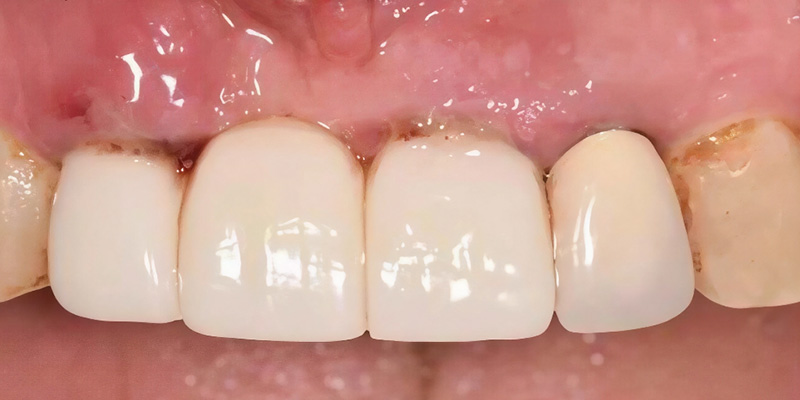

Fig. 1 : Vue préopératoire antérieure.